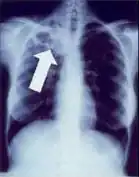

Chest X-ray and CT

Tuberculosis creates cavities visible in x-rays like this one in the patient's right upper lobe.

In active pulmonary TB, infiltrates or consolidations and/or cavities are often seen in the upper lungs with or without mediastinal or hilar lymphadenopathy or pleural effusions ( tuberculous pleurisy). However, lesions may appear anywhere in the lungs. In disseminated TB a pattern of many tiny nodules throughout the lung fields is common - the so-called miliary TB. In HIV and other immunosuppressed persons, any abnormality may indicate TB or the chest X-ray may even appear entirely normal.

Abnormalities on chest radiographs may be suggestive of, but are not necessarily diagnostic of, TB. However, chest radiographs may be used to rule out the possibility of pulmonary TB in a person who has a positive reaction to the tuberculin skin test and no symptoms of the disease.

Cavitation or consolidation of the apexes of the upper lobes of the lung or the tree-in-bud sign[15] may be visible on an affected patient's chest X-ray.[1] The tree-in-bud sign may appear on the chest CTs of some patients affected by tuberculosis, but it is not specific to tuberculosis.[15]